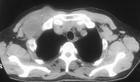

骨神經鞘瘤系骨內神經鞘細胞所產生的良性腫瘤,很少見。好發于下頜骨、骶椎、尺骨干及肱骨干等處,多為20~50歲的青中年男性,腫瘤發展緩慢,病程較長。